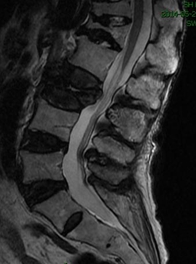

因:“腰椎骨折椎体成形术后2天”入院

患者因“脑卒中后遗症”在我中心康复治疗,于4月27日行走时滑倒腰部跌伤,当时即感疼痛,活动受限,到当地医院就诊,经CT等检查后,诊断为L3骨折,予卧床休息、口服活血化瘀及镇痛等对症治疗,患者自觉症状无改善,于6月03日在上级医院行椎体成形手术,2014年6月04日再次转入我中心继续康复治疗。患者入院时腰背部疼痛明显改善,并可下床活动。

入院诊断:(1)腰椎骨折术后